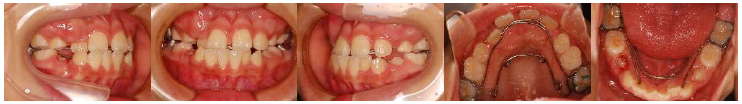

治療開始2か月後。

治療開始3か月後。